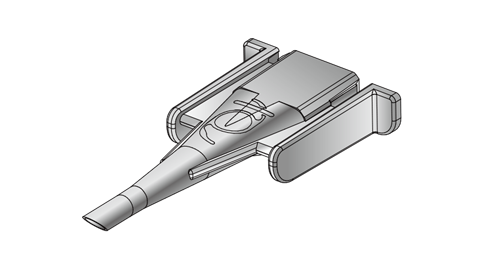

Eyebright Medical Technology (Beijing) Co., Ltd. (“Eyebright Medical”; SH Stock Code: 688050) is a National High-tech Enterprise and state-level technologically advanced "Little Giant" enterprises, located in Zhongguancun Science and Technology Park, Beijing, China. The Company is an innovation-driven ophthalmic medical device manufacturer. Its balanced product portfolio spans three major areas of the ophthalmic field: surgical treatment, myopia management, as well as consumer vision care. Anchored by its three core product categories - intraocular lenses, orthokeratology lenses, and soft contact lenses - the company has strategically expanded its product pipeline to cover the full life cycle of eye health solutions. Eyebright Medical is striding into a world-leading medical enterprise on behalf of China’s "Intelligent Manufacturing" power.